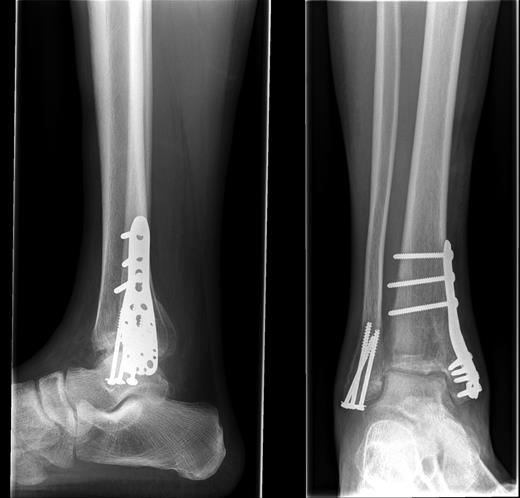

The fracture was unstable and required fixation, but due to extensive soft tissue damage and swelling and a lack of sickle cell testing, the operation was delayed for 6 days (Fig. 2). The operation was performed under a General Anaesthetic with Popliteal Block with the patient supine and a sandbag placed under the right buttock. A tourniquet was applied and a lateral approach to the fibula was taken with standard washout and fracture reduction achieved. The distal fibular fracture was fixed using three partially threaded cancellous screws.

The distal tibia was approached via a direct medial approach. This revealed an extensively comminuted fracture extending proximally. The fracture site was identified, reduced and held in place with 2 × 2.0 mm k-wires. This medial fracture was not amenable to screw fixation or tension band wiring; an LCP plate was applied which did not have an adequate fit. A four-hole medial distal tibial LCP was not available. The next alternative was to use a PHILOS plate as it appeared to fit the contours appropriately. An intraoperative decision was made to use a 3.5 mm LCP® Proximal Humerus Plate (PHILOS) plate. The plate fit the distal tibial contours well once the fracture was reduced. Three proximal non-locking cortical screws and multiple distal locking screws were applied producing a stable construct (Fig. 2).